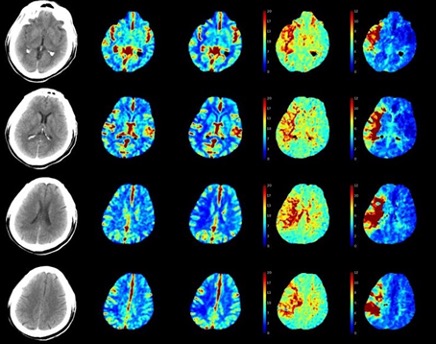

CT perfusion quantifies cerebral blood volume (CBF) mean transit time for blood flow through brain tissue. This is done through a repeated series of scans through the anterior circulation over 1 minute after a bolus of contrast is administered. We watch the bolus go through the vascular territory. This is useful to identify alterations in cerebral blood flow to distinguish the infarct from the penumbra. It is 6x more radiation, needs to be interpreted by software to get color coded, and may result in some false positives and negatives. Useful for patients who are 6-24 hours from LKW to see if they are a candidate for a thrombectomy.

Perfusion weighted imaging (PWI) depicts areas with reduced cerebral blood flow. A DWI-PWI mismatch can estimate an area of brain tissue at risk of infarction (penumbra) if blood flow not restored.